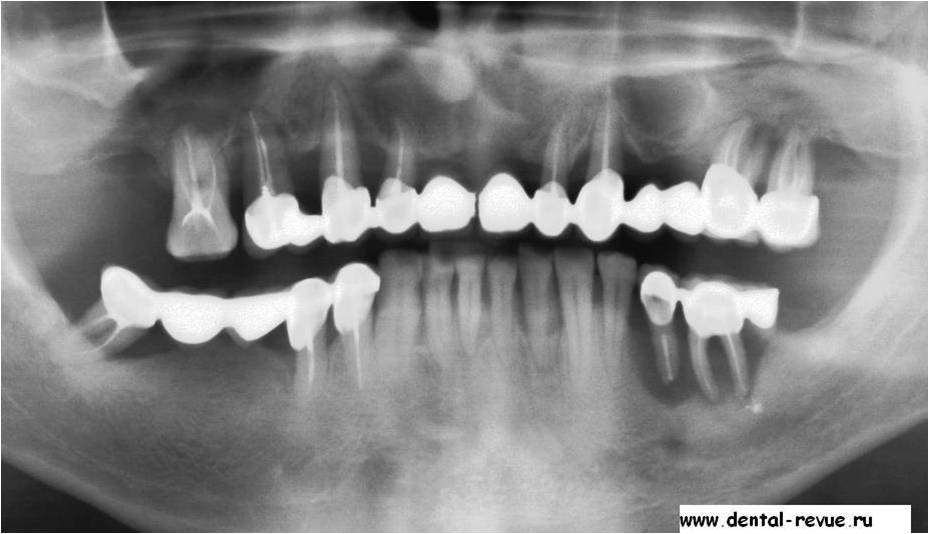

Вид больных и протезированых зубов, вы хотите себе такие зубы уже в молодом возрасте.